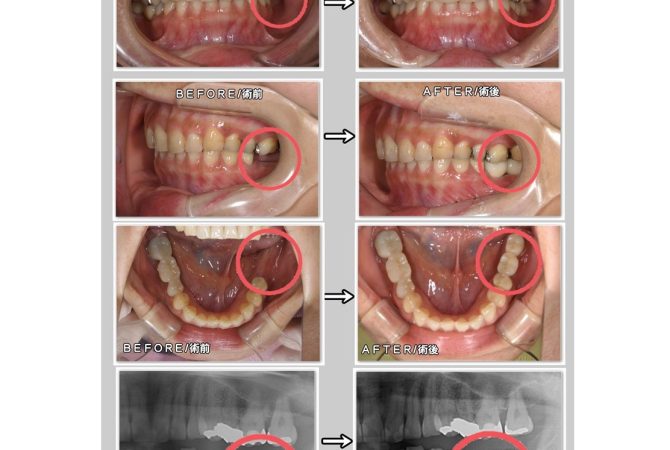

2026.2.9 症例 インプラントの症例 GBR法/骨補填材使用 詳しく見る 2026.1.13 学び インプラント学会の試験受験★ 詳しく見る 2025.12.27 症例 インプラントの症例 詳しく見る 2025.12.13 学び インプラント学会の予備試験受験&インプラント周囲炎の治療セミナー参加☆ 詳しく見る 2025.11.30 症例 インプラントの症例 GBR法/骨補填材使用 詳しく見る 2025.11.20 院内のこと インプラント手術 詳しく見る 2025.11.1 症例 インプラントの症例 GBR法/骨補填材使用 詳しく見る 2025.10.31 学び インプラント のための骨造成セミナーを受講 詳しく見る 2025.10.7 学び インプラント のセミナーに参加してきました 詳しく見る 1 / 3 ページ23次へ »